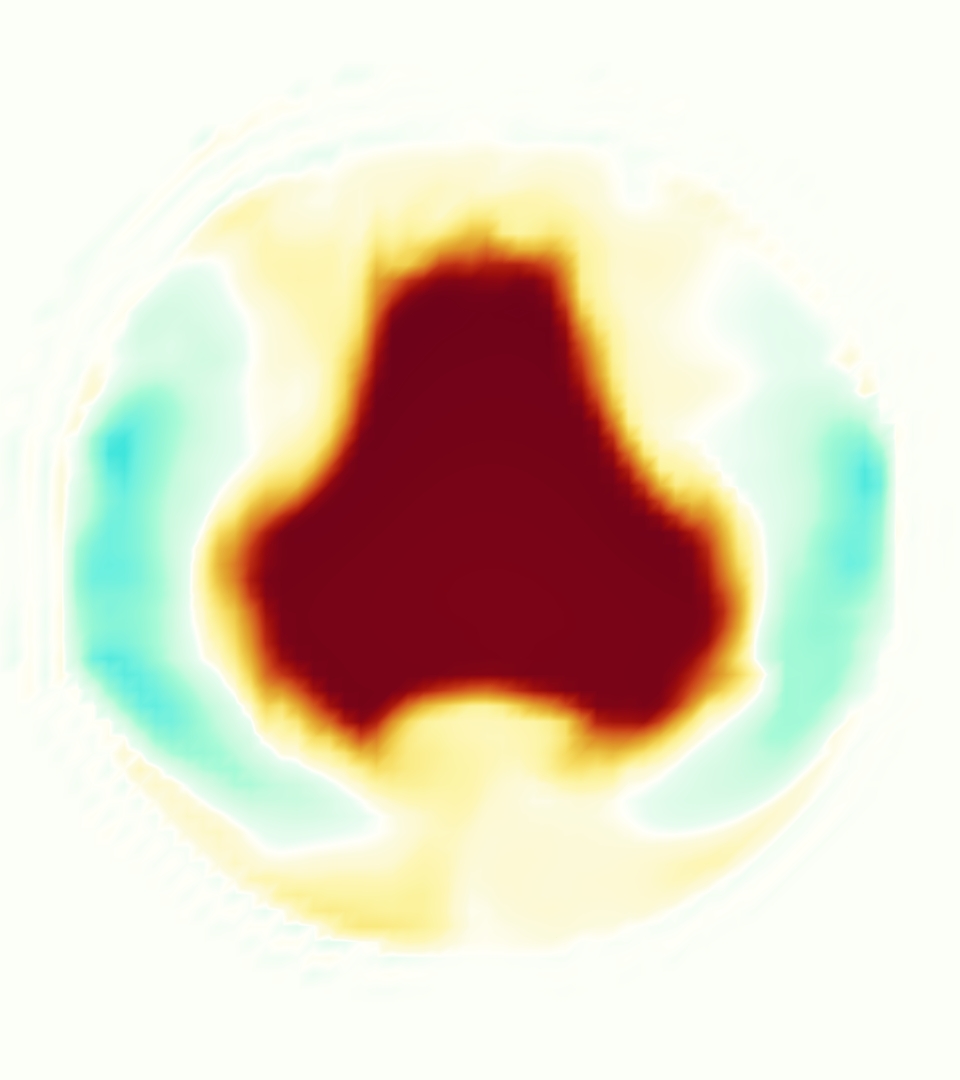

The emergent hemodynamics showed excellent qualitative agreement with experiments. Slice views of the axial component of fluid velocity ( component) in the sagittal plane that cuts through the center of the vessel, parallel to the flow direction, are shown in Figure 5. The flow in both the simulation and the experiment began to accelerate at the same time, with a jet forming through the open valve leaflets. The velocity, angle, and shape of the jet agreed well between the two cases during systole. The simulation captured the slight upward angle of the jet, which was not fully centered in the vessel. It also matched the location where the jet impacts the wall and the slower speed of the jet as it turns with the MPA downstream. As the flow decelerated, the fluid along the interior curve of the vessel reversed first while forward flow persisted where the jet was strongest, as seen in both the simulation and experimental results.

In both the experiment and the simulation, a separation region of reverse flow developed along the interior curve of the vessel under the core jet through the valve. The reverse flow began to develop at the same time in the cardiac cycle and grows throughout systole. The simulation lacked reversed flow in the entire region where reversed flow was present in the experiment, but this region developed some flow separation and had much slower flow than elsewhere in the vessel. Thus, the simulation captured that this is a distinct region from the core jet through the valve opening. There was a smaller amount of slower and slightly reversed flow along the outer curve of the vessel, close to the valve annulus and scaffold support. This region was well-matched between the experiment and the simulation.

Slice views of the (axial) component of fluid velocity in the axial plane, orthogonal to the flow direction, show that the simulation replicated the development of the jet over the cardiac cycle. At each phase, the simulation matched the forward speed of the core of the jet and the locations of reverse flow back towards the valve annulus. While there are some differences in the shape of the jet at certain phases and locations, the simulation clearly produced the general dynamics of the cardiac cycle that are seen in the experiment.

At = 0, the axial slice directly at the valve annulus shown in columns 1 and 2 in Figure 6, there was excellent agreement between the simulation and experiment over the cardiac cycle in the speed and shape of the jet through the valve. In both cases, the axial velocity increased as the flow accelerated during systole and the valve leaflets opened, then decreased during diastole with slight negative velocity before the valve leaflets were fully closed. The forward flow through the valve annulus did not form a full circle, but rather developed a triangular shape with a point of the triangle forming along the interior curve of the vessel, at the bottom of the axial slices. At = 0, the points of this triangular jet shape aligned with the commissures of the valve. This shape persisted during peak systole and was well-matched by the simulation.

The axial slice = 0.625 cm, shown in columns 3 and 4 in Figure 6, cut through the support scaffolding of the valve and the leaflets when they are open. In the experimental data, the shape of the jet changed as it moved downstream. A triangular shape occurred, but the points were then aligned with the middle of each open leaflet as opposed to the commissures. Those points were also more rounded than they were at = 0. The peak velocity of the jet was faster at = 0.625 cm than at = 0, as the flow accelerated through the open valve leaflets. The simulation produced these features at = 0.625 cm. The triangular shape of the jet shifted similarly, and its speed increased compared to the upstream slice. As the flow decelerated into diastole, the jet shape remained roughly triangular but diminished in intensity before disappearing after valve closure.

The jet continued to develop at = 1.25 cm, an axial slice immediately downstream of the valve scaffolding and open leaflets, shown in columns 5 and 6 in Figure 6. In the experimental data, the points of the triangular jet shape extended further towards the vessel wall. In addition, regions of reversed flow developed in the locations downstream of the commissures, resulting in curved sides to the shape of the jet. Each tip of the jet was unique, due to variations in the individual leaflets in the physical bioprosthetic valve. These variations are apparent in the velocity fields, possibly because the jet edges are similar enough cycle to cycle that irregularities are still being captured even with phase averaging. Further discussion of these features can be found in Schiavone et al. [39], which showed that the jet tip shapes occurred in different pulmonary anatomies, demonstrating that they were likely due to inherent properties of each leaflet. The leaflets in the mathematical model of the valve are identical, so these nuances in leaflet variation could not be replicated. The simulation did capture some of the extension of the tips of the jet, as they were closer to vessel wall at slice = 1.25 cm than = 0.625 cm. The curves in the triangular sides of the jet were also present in the simulation, though they were less pronounced than the experimental data. At both = 0.625 cm and = 1.25 cm, the jet shape in the simulation was smoother than the jet in experiment. It is possible that the free edges of the leaflets in the mathematical model are not fully replicating the behavior of the physical leaflets of the bioprosthetic valve, in particular the amplitude or frequency of leaflet flutter, leading to the variations seen in the jet shape at = 1.25 cm downstream of the leaflet edges. The simulation, however, does capture the key features of the triangular shape and speed of the jet. Overall, qualitative comparisons demonstrated that the simulation reproduced key features of the flow during systole and diastole.